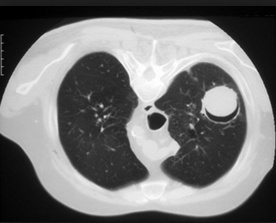

farmer on left. Cactus: fungus balls. Aspergillomas form in cavities, such as in TB/klebsiella cavities. People with cavities in lungs already are at risk

peanuts underground: Aspergillomas are gravity-dependent, fungus at bottom of cavity on chest xray

cannon balls in lung: Lesions or cavities in lungs

lung wall holes, bricks caved in/out: Radiographic images may show either nothing or cavities and/or nodules.